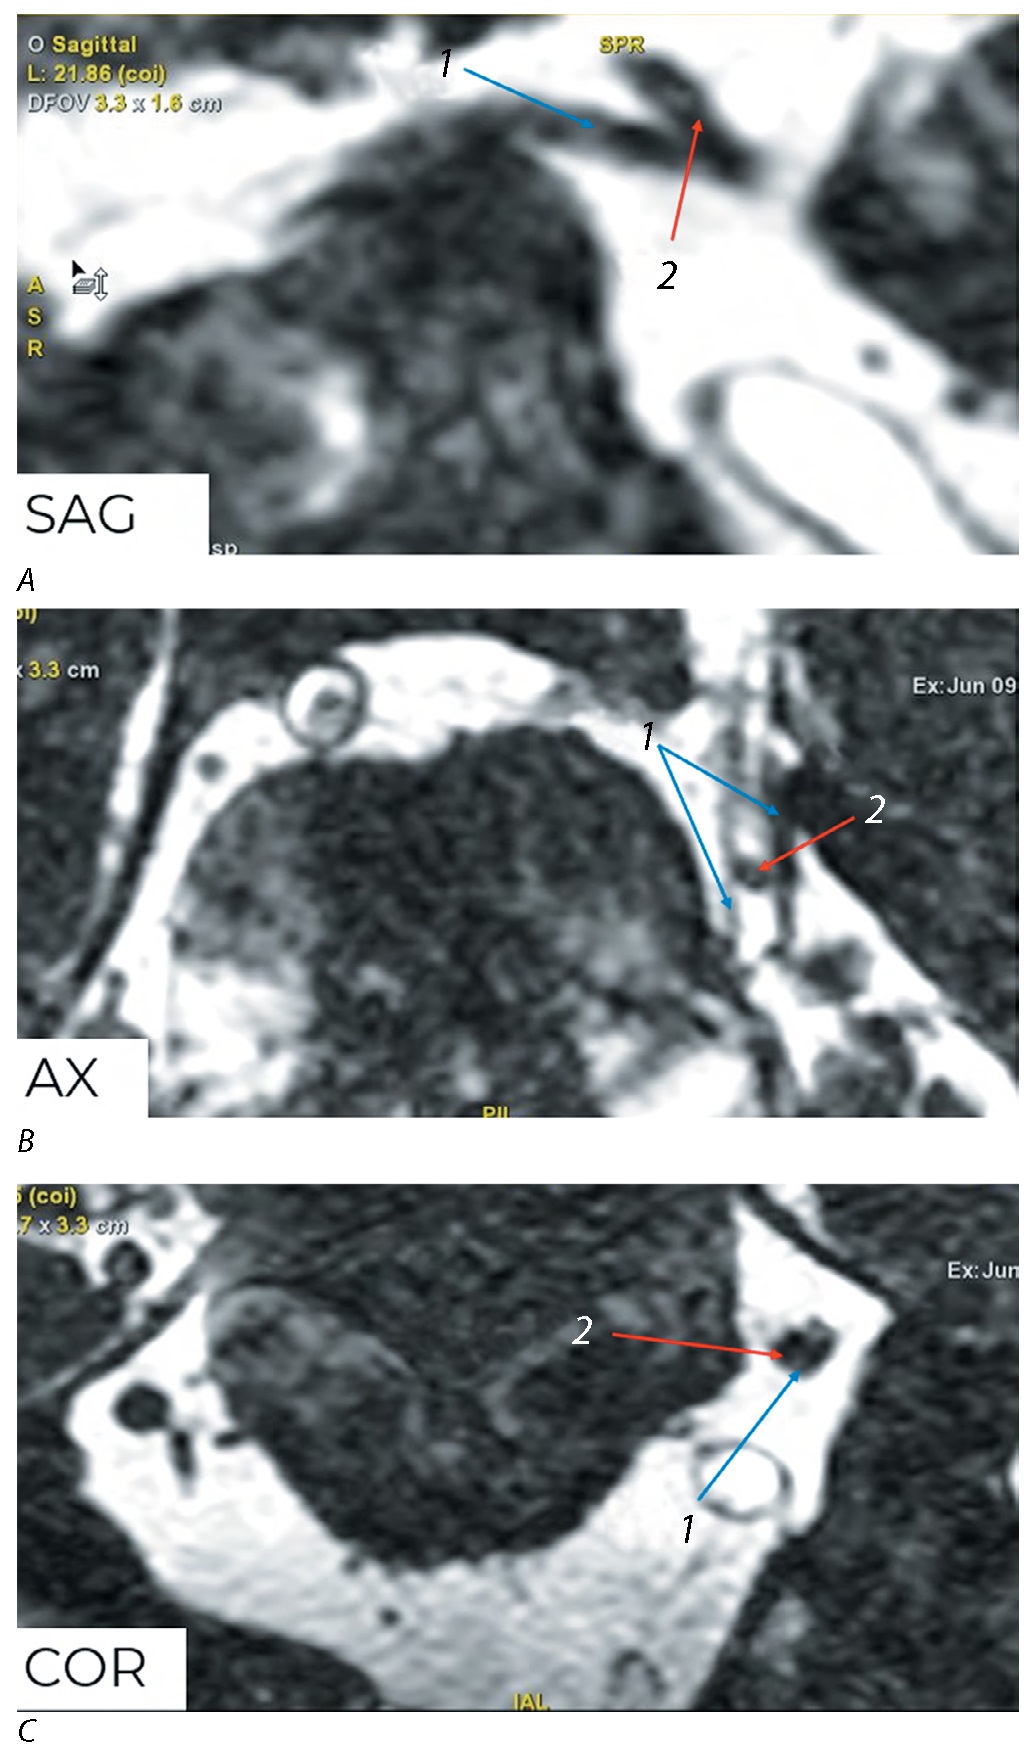

Снижение ФА на симптомной стороне диагностировано у 80,5% пациентов 1-й группы (рис. 3, 4) и у 100% пациентов 2-й группы. У остальных 19,5% пациентов 1-й группы показатель ФА повышен на стороне клинических проявлений, что не соответствует наличию структурных изменений в данном корешке нерва.

Рис. 3. МРТ головного мозга, режим FIESTA.

А — сагиттальная плоскость изображения; В — аксиальная; С — коронарная. Прободение корешка левого ТН (1) верхней мозжечковой артерией (2), III степень по М. Sindou.

Fig. 3. Brain MRI, FIESTA sequence.

А — sagittal plane; В — transverse plane; С — frontal plane. The left trigeminal nerve root (1) perforated by the superior cerebellar artery (2), Sindou's сompression severity III.